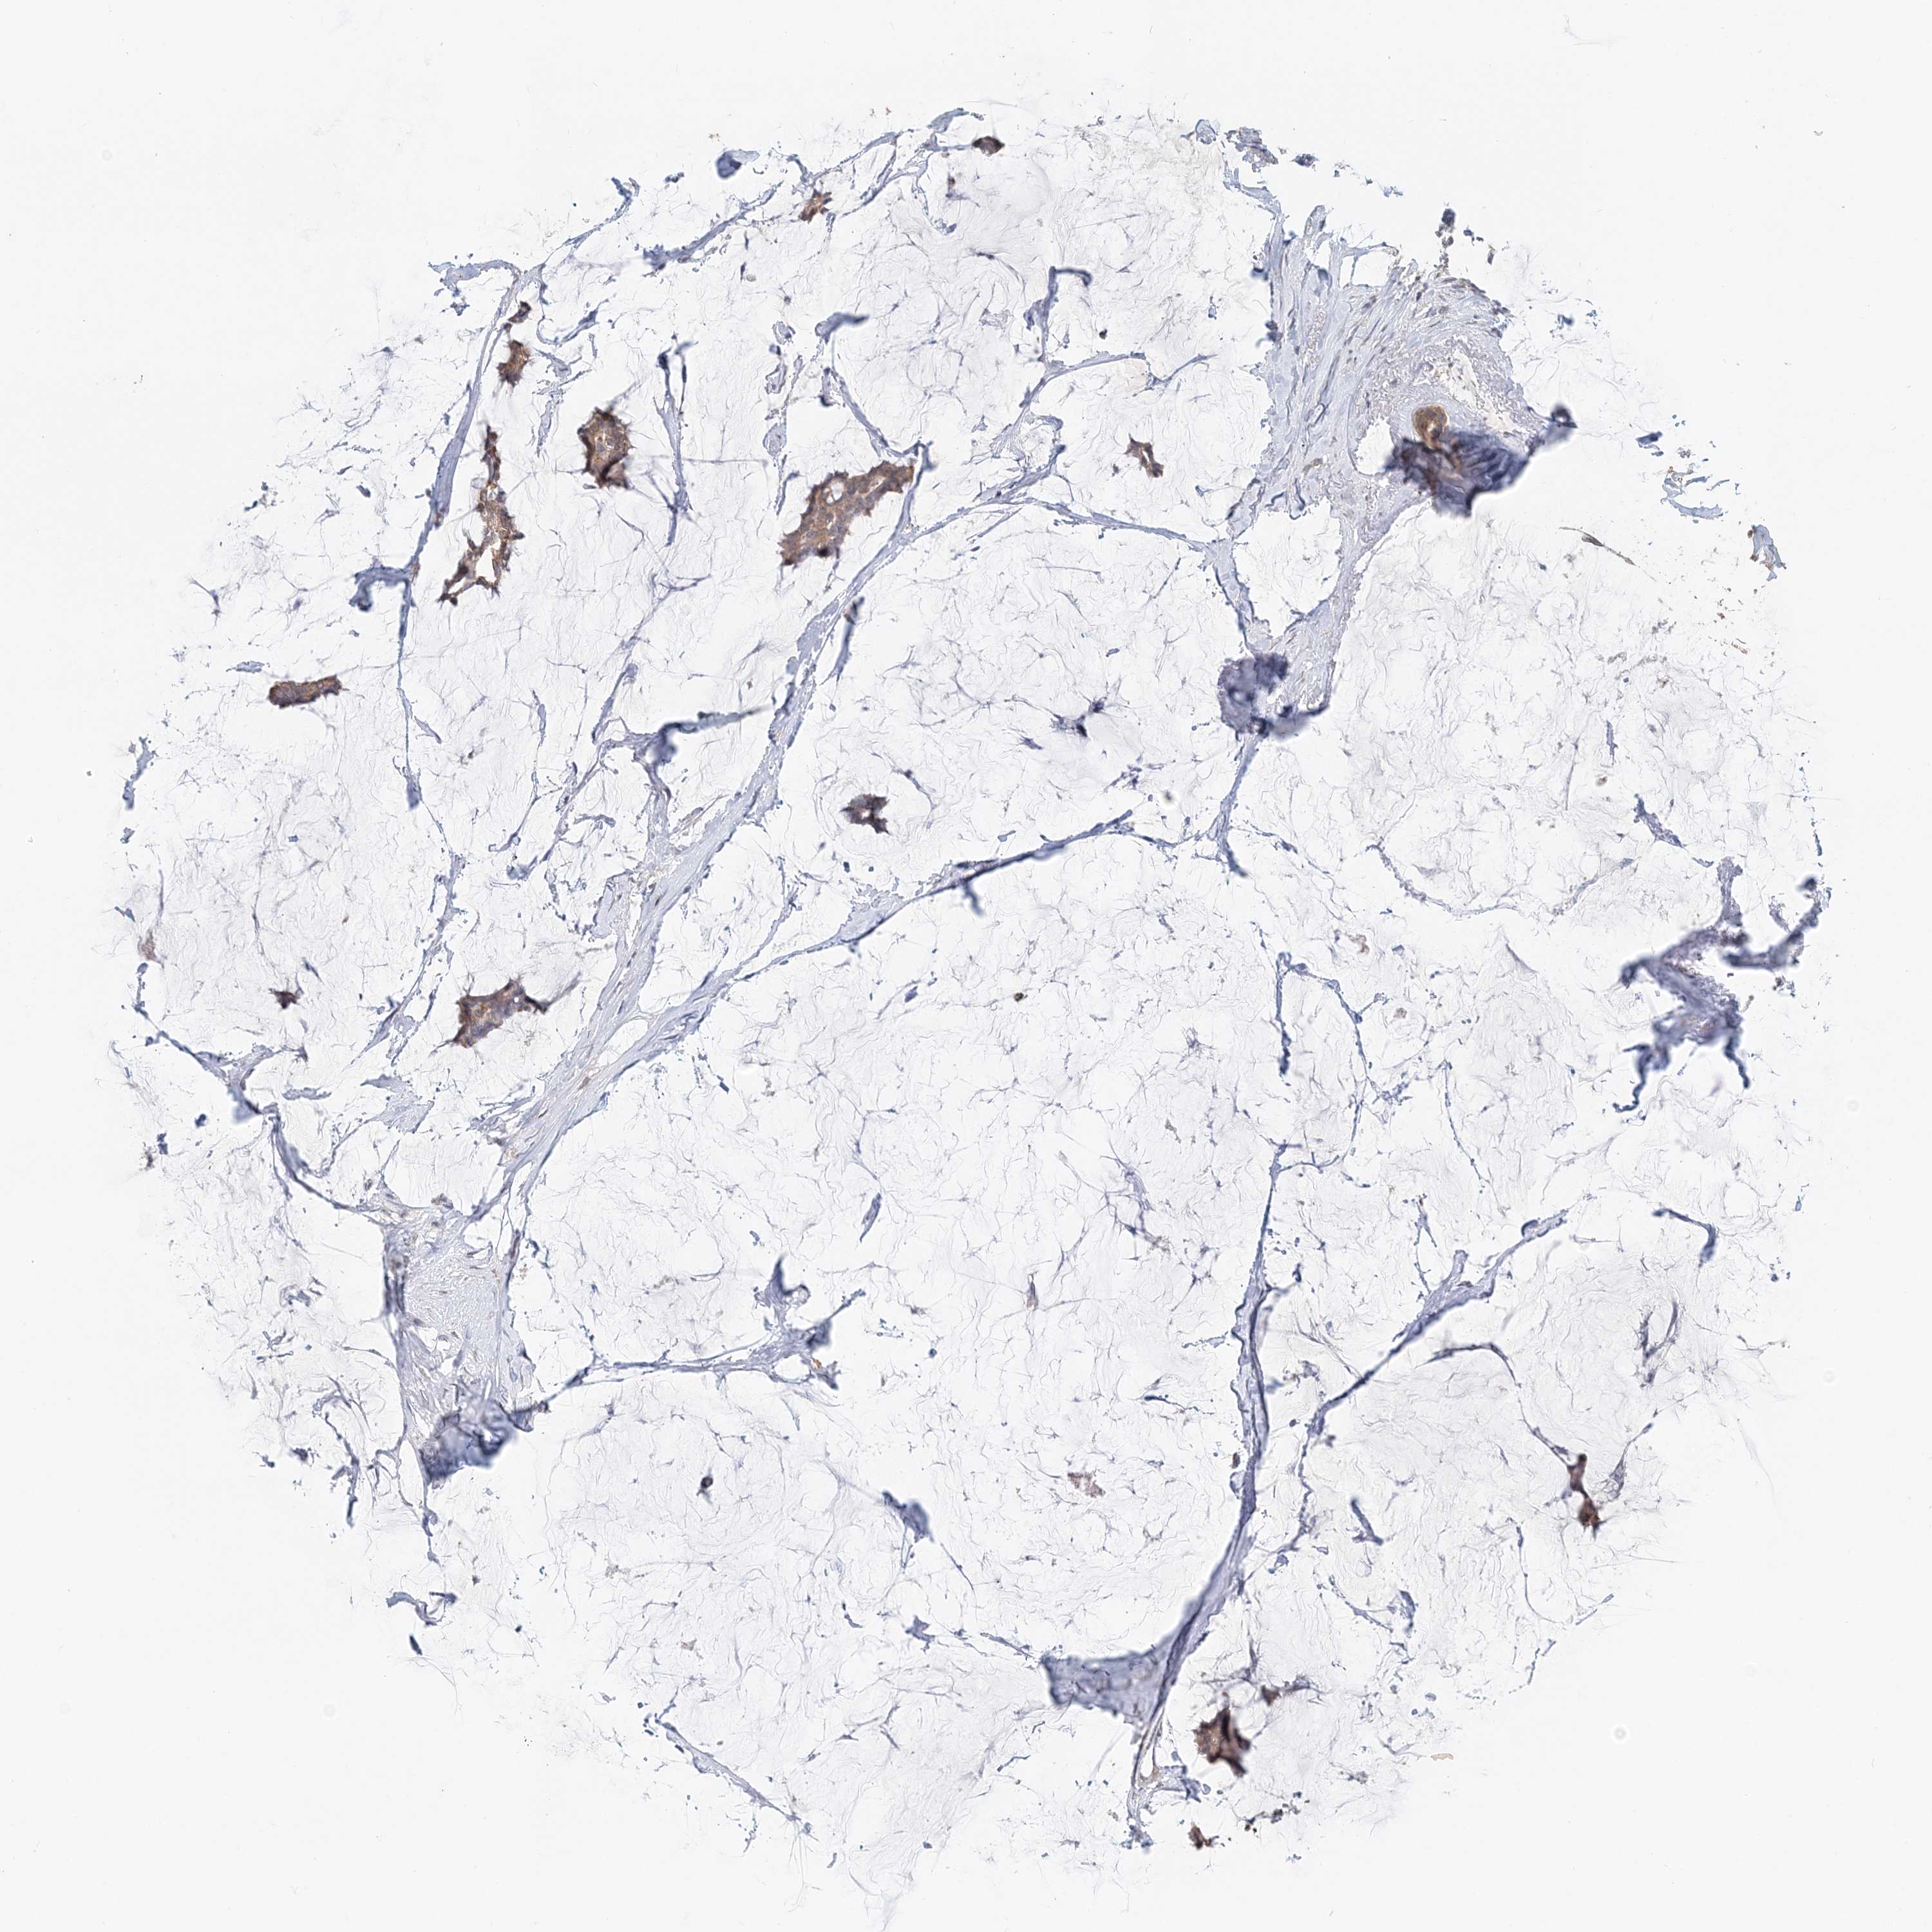

CANCER BREAST CANCER Show tissue menu

BRCA TCGA BRCA VALIDATION PROTEIN EXPRESSION

Breast cancer

Human cancer